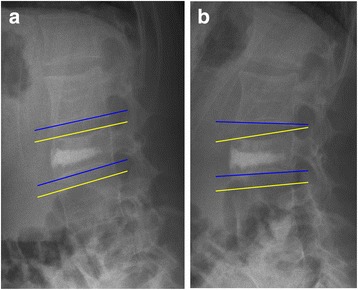

On roentgenograms at latest follow-up no spontaneous fusion was observed. However residual mobility (Fig. 6) was observed in six patients out of the eight patients in whom flexion-extension radiographs were obtained. This residual mobility was most pronounced in the distal adjacent segment, although as seen in Fig. 6 it was present at the proximal adjacent segment as well.

Fig. 6.

Flexion- (a) and extension (b) roentgenograms after removal of the instrumentation visualizing residual mobility